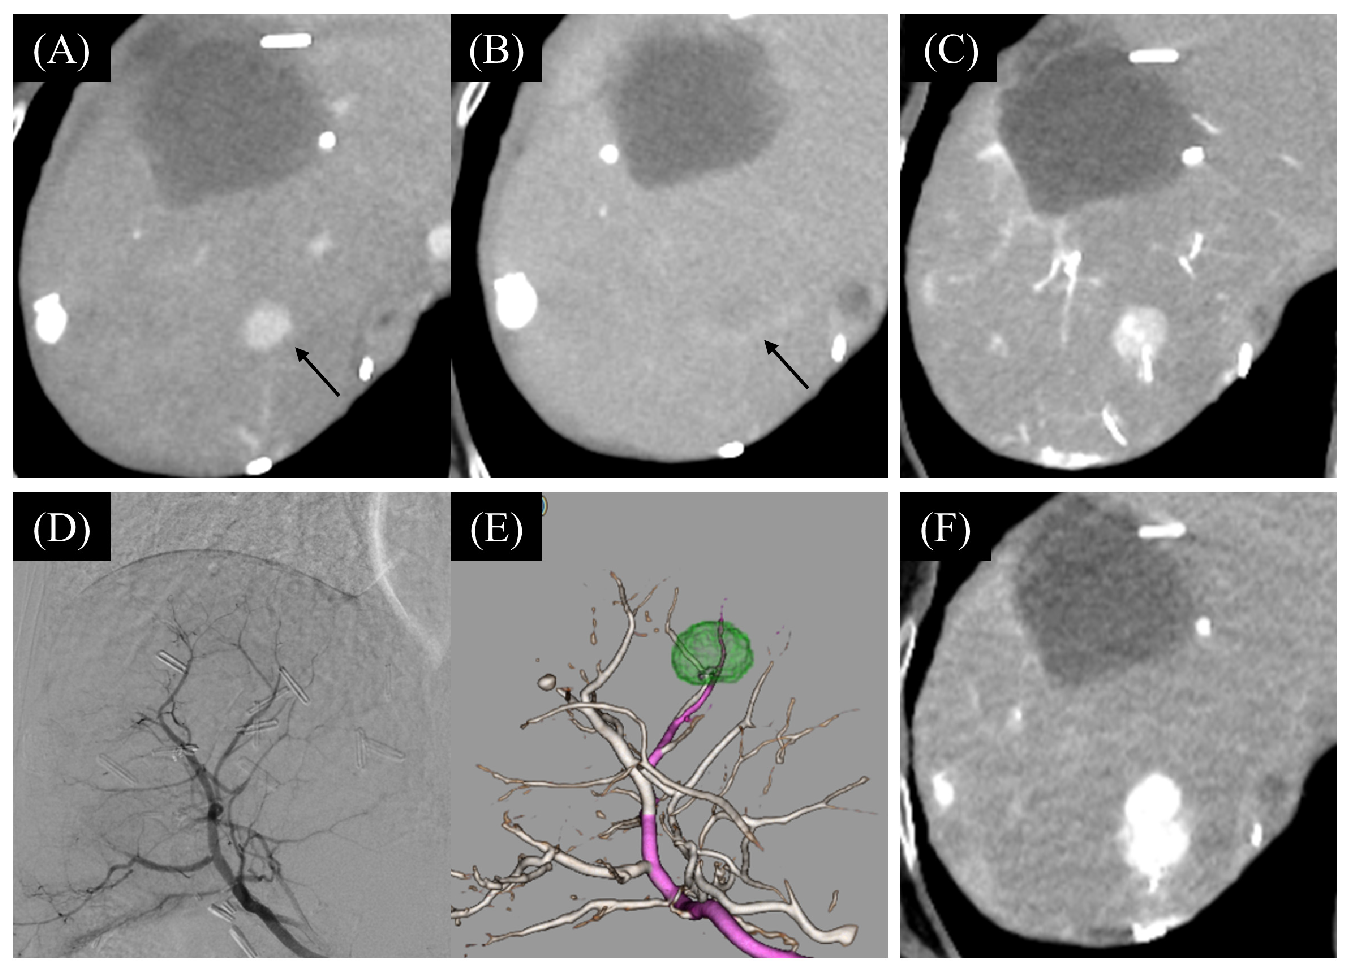

- Tachiiri, T.; Nishiofuku, H.; Maeda, S.; Sato, T.; Toyoda, S.; Matsumoto, T.; Chanoki, Y.; Minamiguchi, K.; Taiji, R.; Kunichika, H.; et al. Vascular Normalization Caused by Short-Term Lenvatinib Could Enhance Transarterial Chemoembolization in Hepatocellular Carcinoma. Curr. Oncol. 2023, 30, 4779–4786. [Google Scholar] [CrossRef]